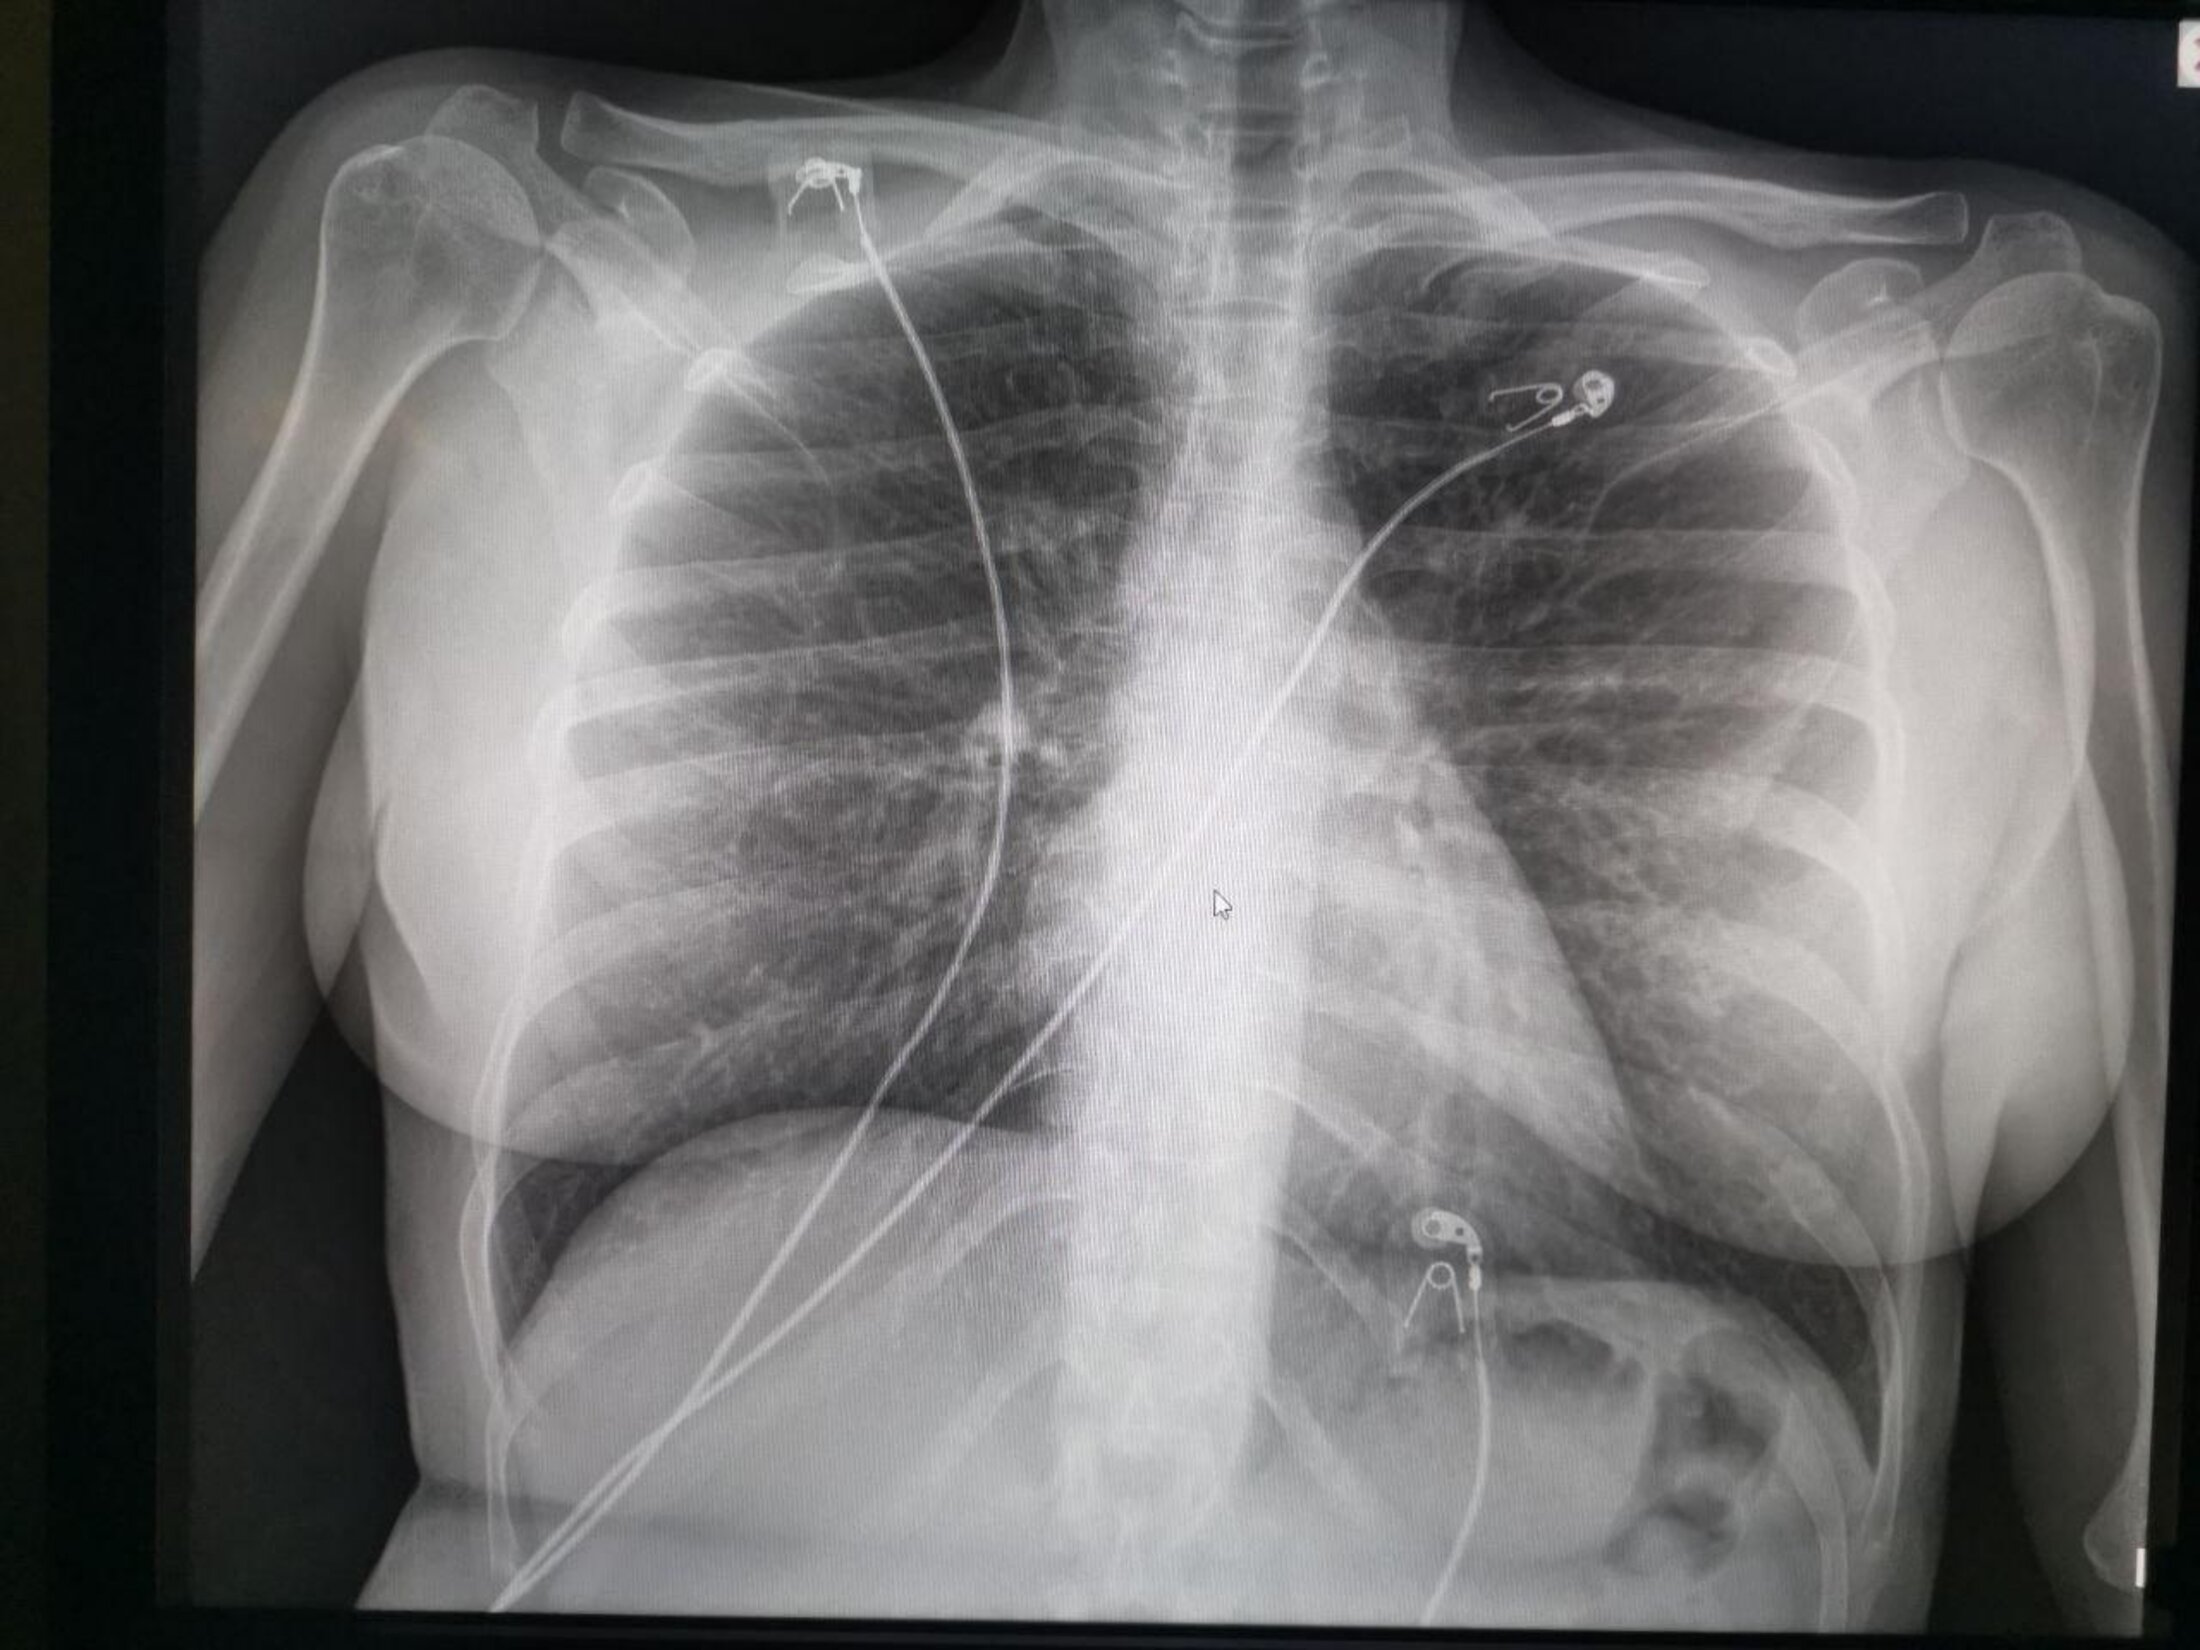

Agrandissement : Illustration 4

A chaque box, je change de surblouse et je jette la 2ème paire de gants, à chaque box je nettoie l’appareil.